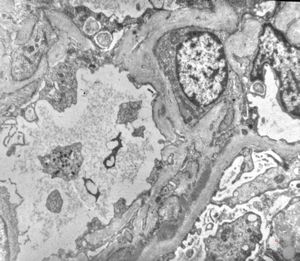

M,53y. | type III membranoproliferative glomerulonephritis